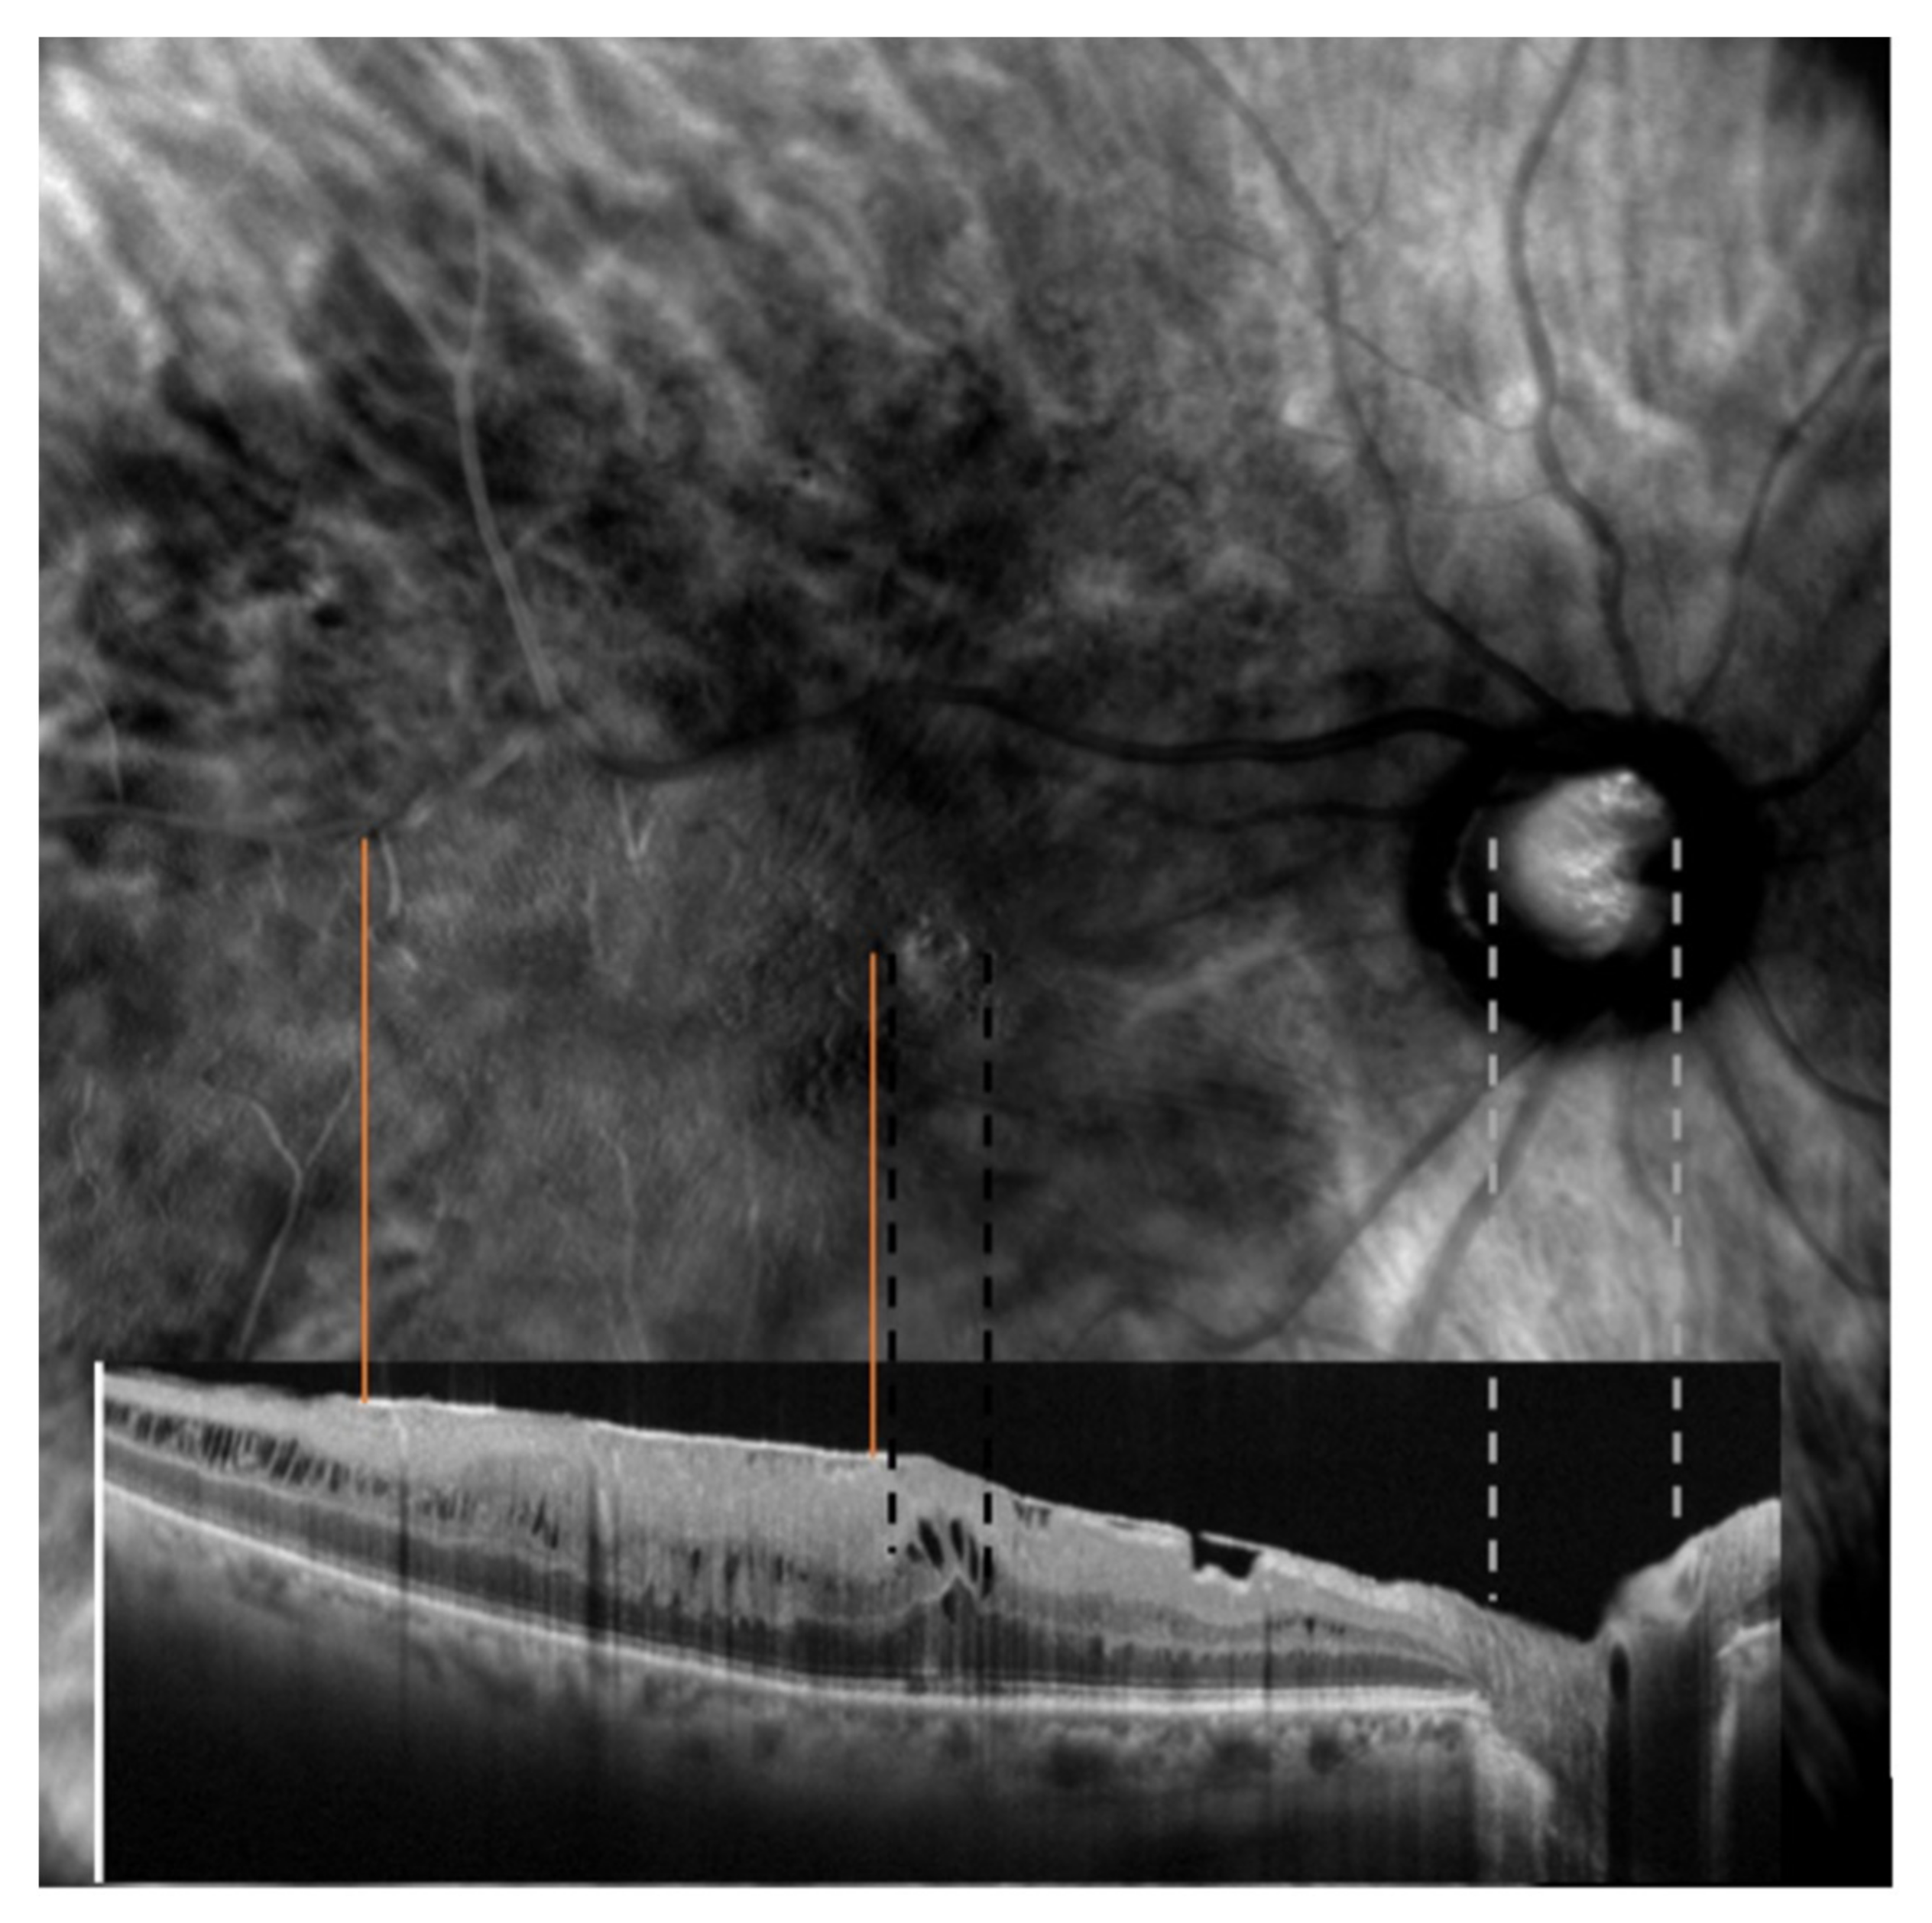

The optic nerve’s superior and inferior margins and retinal blood vessels on color fundus photography (blue lines and orange lines, respectively) were matched with their counterparts identified on retromode images, as shown in Figure 1. On the other hand, while FAF images were matched to retromode images using the retinal blood vessels alone (orange lines Figure 2), for OCT B-scans we used both the neuroretinal rim (grey lines) and the extension of the ERM itself. Particularly, the ERM margins on OCT images were projected onto the retromode image through orange lines, whereas black lines parallel to those originating from the neuroretinal rim were used to project the cystic spaces identified on OCT B-scans to their retromode counterparts (Figure 3).

Figure 3. Retromode and SD-OCT correspondence: neuroretinal rim on optical coherence tomography (OCT) scan (grey lines) used as reference points to check for appropriate image matching. Dashed black lines represent the extent of the cystoid spaces.